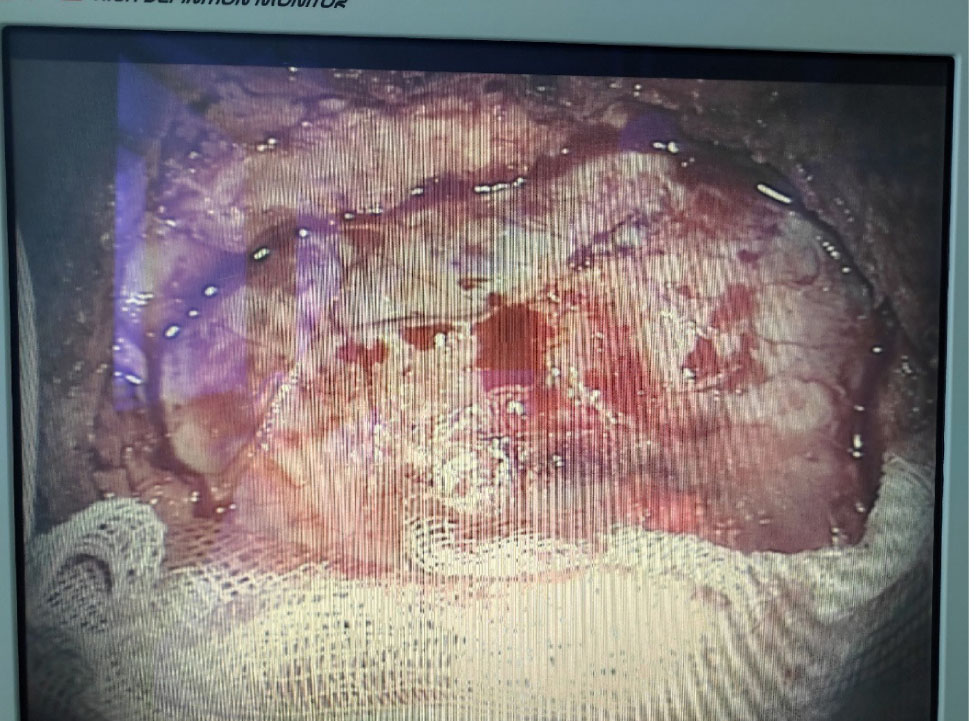

Морфологические характеристики ТМО. ТМО представляет собой белого цвета блестящую пластинку внутри и матово-серую снаружи. Она достаточно гладкая на ощупь и состоит из рыхло спаянных между собой двух листков, которые легко отделяются друг от друга – это надкостничная часть оболочки и менингеальная часть (рис. 1, 2) [11].

Рис. 1. ТМО мужчины 56 лет после извлечения головного мозга из полости черепа

Рис. 2. Фотоизображение ТМО мужчины 40 лет с экрана микроскопа при оперативном вмешательстве с целью удаления мешотчатой аневризмы